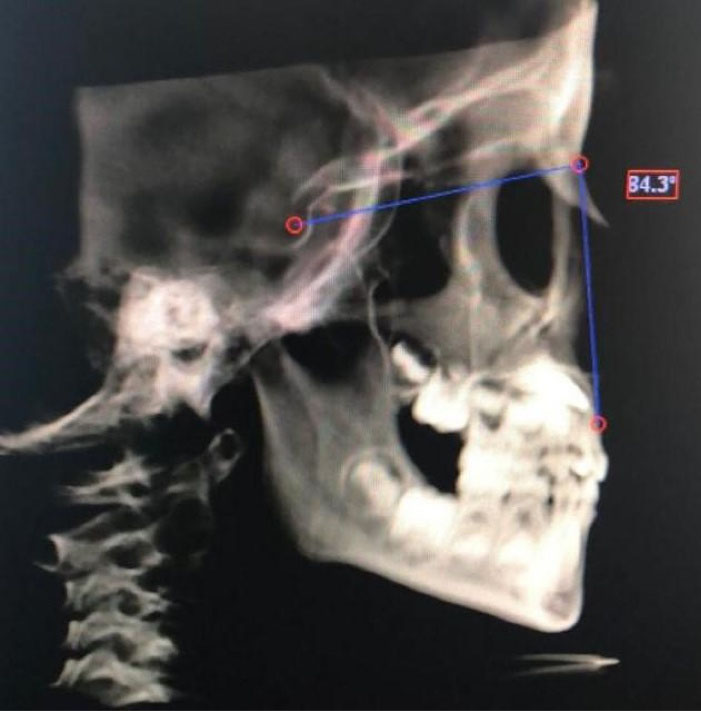

Figure 3.

Measurement of SNB angle.

| SNB | The angle created between sella, nasion, and B points |